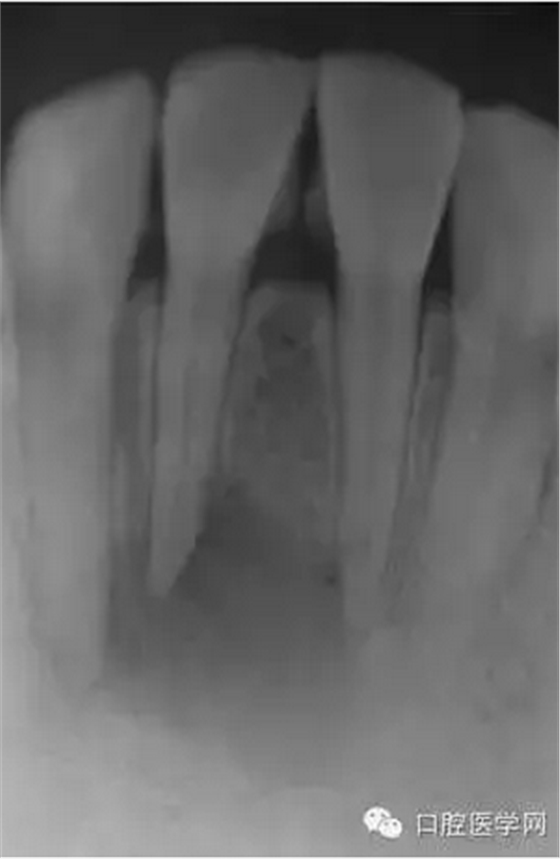

23歲女性患者,下頜右前牙的唇側(cè)有嚴(yán)重腫脹和疼痛。相應(yīng)部位有過外傷史,但記不起是什么時候了。放射線照片顯示以右下頜中切牙為中心,有波及右下側(cè)切牙及左下中切牙的大范圍的根尖周病變,臨床檢查時,無齲壞,只發(fā)現(xiàn)右下中切牙略有變色,牙髓活力檢查(電子牙髓檢查及冷檢查)發(fā)現(xiàn),右下中切牙無反應(yīng),而鄰近齒表現(xiàn)為正常。判斷大范圍的根尖周病變的原因是受過外傷的右下中切牙的牙髓壞死,受周邊環(huán)境影響,發(fā)展為急性根尖周膿腫。

(圖 1) 初診的放射線照片